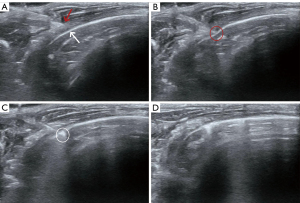

Characteristics observed via B-mode ultrasound included the lesion size, presence of pleural effusion, relative movement between subpleural lesions and the chest wall, and communication region between the lesion and the parietal pleura. Lesion size was determined by measuring the maximum diameter of the lesion on ultrasound. As the movement of the lesion could be affected by the respiratory state of the rabbit, the movement was only used as an indicator of suitability for CEUS and not as a standard to confirm whether the lesion was adhesive or invasive. Analysis of adhesion/invasion via B-mode ultrasound analysis of was mainly conducted by observing whether there was an adhesion/invasion zone between the lesion and the parietal pleura. A contiguous band between the two indicated adhesion/invasion; while a mass and a parietal pleura that were smooth and not clearly connected indicated noninvasion.

No immediate pneumothorax or hemorrhage was observed in any rabbit following ultrasound-guided injection. However, three rabbits died under anesthesia before ultrasound evaluation, and an additional three rabbits died during feeding within 1–3 weeks after model construction. Ultimately, 34 rabbits were subjected to complete ultrasonic evaluation. Within 10–14 days after tumor injection, ultrasonography detected subpleural lung cancer in all 34 rabbits (15 left lesions and 19 right lesions), indicating a 100% tumor formation rate. There were 20 and 14 cases of subpleural lesions with and without parietal pleural adhesion/invasion, respectively, confirmed by anatomical and/or pathological assessments. Among the 14 cases without adhesion/invasion, lesions were observed on days 7, 14, and 18 after tumor injection in 7, 6, and 1 cases, respectively (see Figure 2). Among the 20 cases with adhesion/invasion, parietal pleural adhesion/invasion was observed on days 14, 18, and 21 after tumor injection in 4, 8, and 8 cases, respectively (see Figure 3).

Ultrasonography cannot discover lesions within the lung due to interference of lung gases, leading to its underutilization in diagnosing thoracic tumors. However, the chest wall, pleura, and subpleural lung tumors are not impacted by lung gases, and their locations are shallow (see Figure 2). Therefore, the association between subpleural lung cancer and the parietal pleura, such as adhesion/invasion, can be investigated by ultrasound. Researchers have reported B-mode ultrasound to be more accurate than CT in diagnosing wall invasion of lung cancer, possibly because ultrasound allows for real-time evaluation of a lesion’s movement (13,14). The weakness in relative movement between lung lesions and the parietal pleura or chest wall is an important imaging feature for diagnosing parietal pleural adhesion/invasion, whether by ultrasound, four-dimensional dynamic-ventilation CT, or dynamic MRI (10-14). However, chest wall invasion represents deep parietal pleural invasion. It remains uncertain whether such weak movement can help diagnose early local parietal pleural adhesion/invasion. In the early parietal pleural adhesion/invasion animal model developed in this study, there was a tendency toward weaker movement in cases involving large-scale or deep invasion. However, such movement may not necessarily be significantly weakened in slight local or early-stage parietal pleural adhesion/invasion. Therefore, in addition to examining lesion movement, observing areas of adhesion/invasion is also critical. In our study, we used continuity of the parietal pleura and communication between lesions and the parietal pleura to determine the accuracy of B-mode ultrasound in diagnosing parietal pleural adhesion/invasion of subpleural lung cancer, ultimately yielding an accuracy of 70.6%, which is slightly lower than previously reported rates. This is likely due to the prevalence of early local parietal pleural invasion in our cases (13,14).

Although B-mode ultrasound has acceptable diagnostic efficacy in diagnosing parietal pleural adhesion/invasion of subpleural lung cancer, employing advanced ultrasound technologies may further improve the diagnostic value of ultrasonography. With the increasing recognition and application of thoracic ultrasound, the value of CEUS in diagnosing lung and pleural diseases has attracted greater attention. CEUS can differentiate benign from malignant lung lesions and lung cancer with pneumonia (22-24). CEUS also has good diagnostic efficacy in differentiating benign from malignant pleural diseases (25,26). However, its value in diagnosing parietal pleural invasion of subpleural lung cancer remains uncertain. This is the first study to investigate the value of CEUS value in evaluating parietal pleural adhesion/invasion of subpleural lung cancer, revealing a sensitivity, specificity, and accuracy of 90.0%, 100.0%, and 94.1%, respectively. We also demonstrated that the accuracy of CEUS was significantly better than that of B-mode ultrasound. One study reported that CEUS is a more valuable noninvasive imaging technique than is B-mode ultrasound for detecting extracapsular extension of papillary thyroid cancer due to its ability to detect abnormal microvascular perfusion at the invasion area (17). The formation of adhesion/invasion is based on the formation of abnormal microcirculation whether in the early or progressive stages. CEUS is convenient and can be performed in real time, and it has high sensitivity in detecting microvascular perfusion. Additionally, CEUS can observe the relative movement between the lesion and chest wall and can also identify areas of early-stage adhesion/invasion, unlike B-mode ultrasound (see Figure 3). Overall, CEUS exhibited excellent diagnostic ability in evaluating parietal pleural invasion of subpleural lung cancer, especially early-stage invasion.